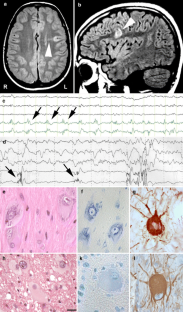

Focal Cortical Dysplasias (FCDs) are highly epileptogenic brain lesions and are a frequent cause for drug-resistant focal epilepsies in humans. FCDs present with variable histopathological patterns, including architectural, cytoarchitectural or white matter abnormalities. Pathomechanisms compromising neuroblast proliferation, migration, or differentiation are likely to play a role in the etiology of FCD variants. FCDs were subsumed, therefore, into the broad spectrum of malformations of cortical development. The most frequent subtype comprises FCD Type II, which in general occurs as isolated lesion in extratemporal location and is histopathologically characterized by dysmorphic neurons (Type IIA) and balloon cells (Type IIB). Neuroimaging hallmarks include hyperintense T2-signaling and a “transmantle sign”. Electrophysiological recordings show peculiar interictal spike patterns and complete surgical resection results in favorable seizure control. In contrast, FCD Type I can be identified in young children with severe epilepsy and psychomotor retardation. Parietal, temporal, and occipital lobes may be involved in seizure generation, although neuroimaging often reveals normal contrast intensities. Surgical resection strategies ameliorate seizure frequencies in many children, whereas complete seizure relief can be achieved only in rare cases. According to the currently used FCD classification system, the same histopathological FCD Type I variant can be diagnosed as associated lesion in the large cohort of epilepsy patients with hippocampal sclerosis, low-grade glio-neuronal tumors, vascular malformations, or glial scarring. MRI is often not helpful to detect the dysplastic cortical areas. In addition, there is no specific electrophysiological pattern for an associated dysplastic lesion. Surgical resection of the epileptogenic area results, however, in favorable seizure control. These findings argue for a revised neuropathological classification system that distinguishes isolated versus associated FCD variants to obtain a better correlation with electro-clinical findings and prediction of postsurgical seizure control.

Fig. 1